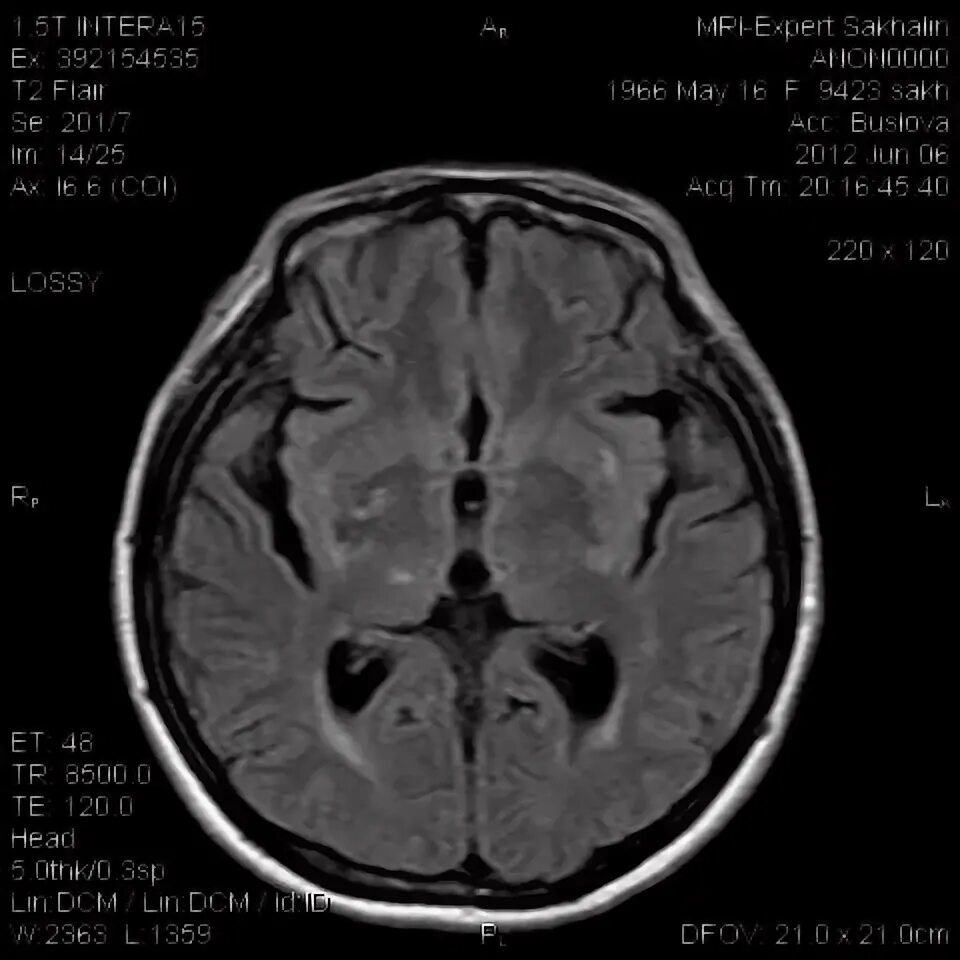

Диффузные изменения вещества головного мозга